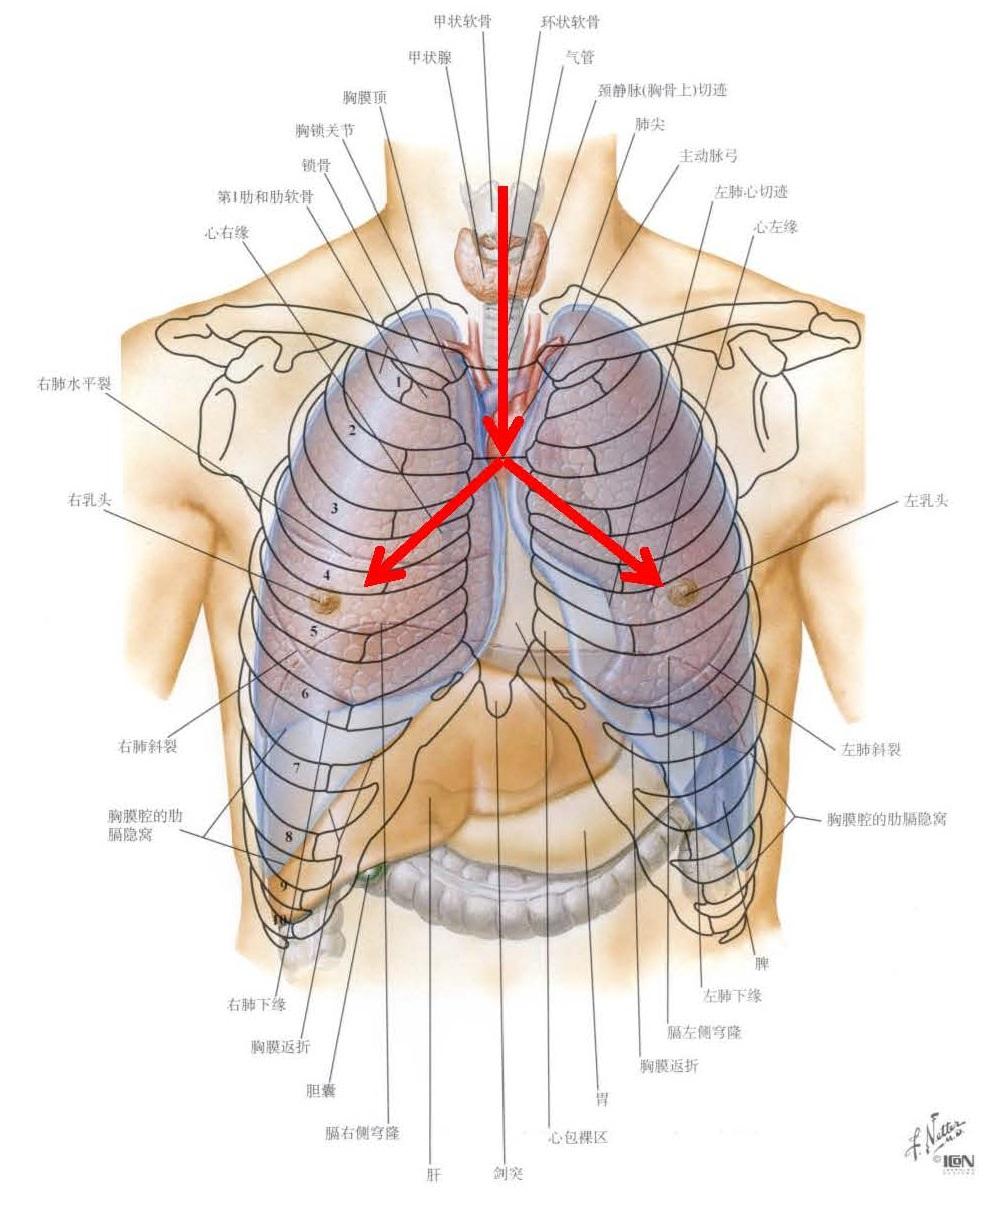

男人肺部在什么位置图

肺在哪个部位?它是干什么的?

好漂亮的肺部解剖!

肺部的解剖结构1